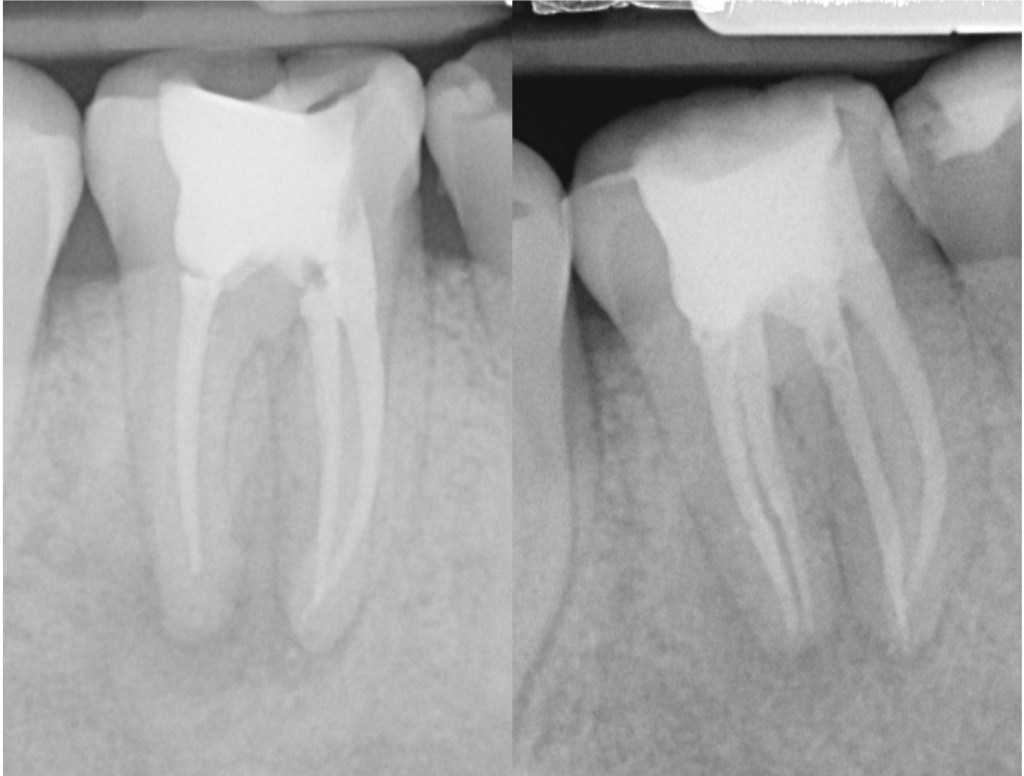

Root canal treatment of the lower right second molar. The curved roots can make cleaning and filling these cases more challenging. Care is taken not to create ledges and blockages in the canal.